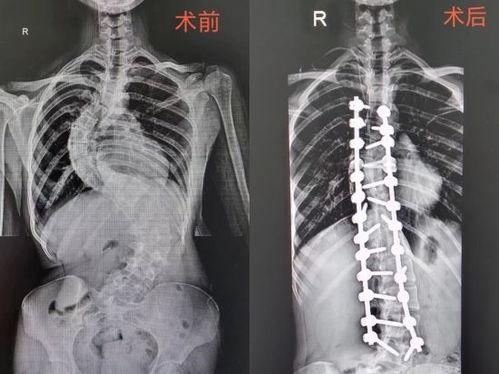

首先,让我们来了解一下什么是脊柱侧弯。脊柱侧弯,顾名思义,就是脊柱在X光片上呈现出的侧弯状态。这种状况可能会影响一个人的外观、姿势,甚至呼吸。据统计,全球约有3%的人患有脊柱侧弯,其中女性患者多于男性。